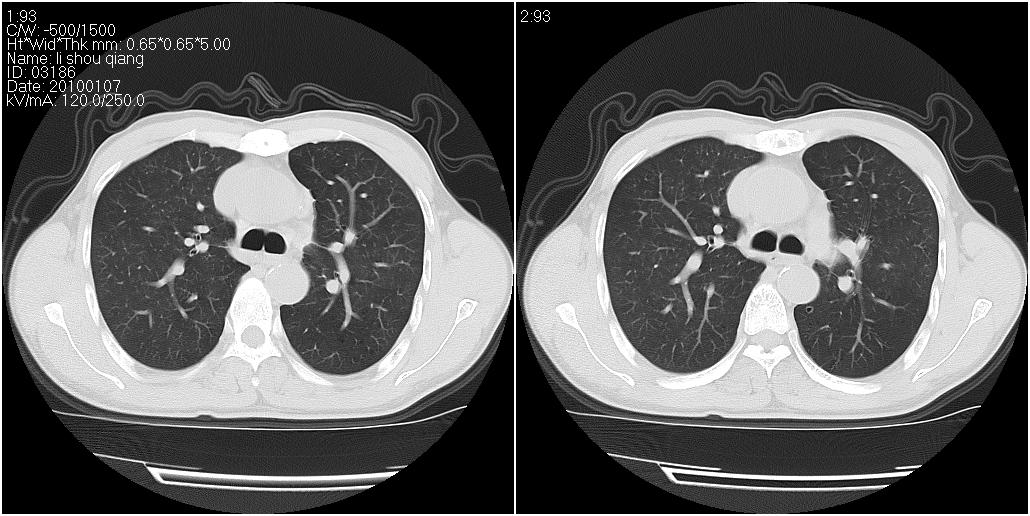

标题: CT24038:男性,58岁。主因咳嗽带血性CT检查。 [打印本页]

标题: CT24038:男性,58岁。主因咳嗽带血性CT检查。

右肺中叶外侧段见一不规则的软组织肿块,边缘可见毛刺,并见厚壁空洞,与胸膜分界欠清。另左下肺见多个小囊状扩张区

右肺中叶外侧段可见团块影,外形不规则,内见空泡征。左下肺见蜂窝状低密度透亮影,部分层面主动脉旁瘤样突出。考虑右肺中叶外围型肺癌可能性大,左下肺支气管扩张,主动脉弓瘤样突出。